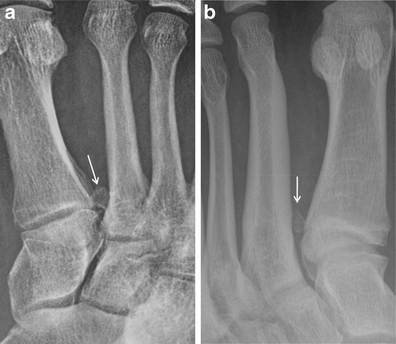

Bipartite versus fractured os peroneum. a Bipartite os peroneum (arrow) with two well corticated, rounded ossicles at the calcaneocuboid articulation. b In comparison, a fragmented os peroneum (arrow) with irregular, angulated edges and displacement, consistent with a fracture

Hallucal sesamoid fracture. Oblique (a) and AP (b) radiographs at the forefoot in a patient after deceleration injury. There are dorsal dislocations of the first and second metatarsophalangeal joints (black arrows), with a comminuted fracture of the lateral hallucal sesamoid (white arrows). Note that the sesamoid fracture pieces would fit together perfectly. The medial hallucal sesamoid is also fractured in this patient